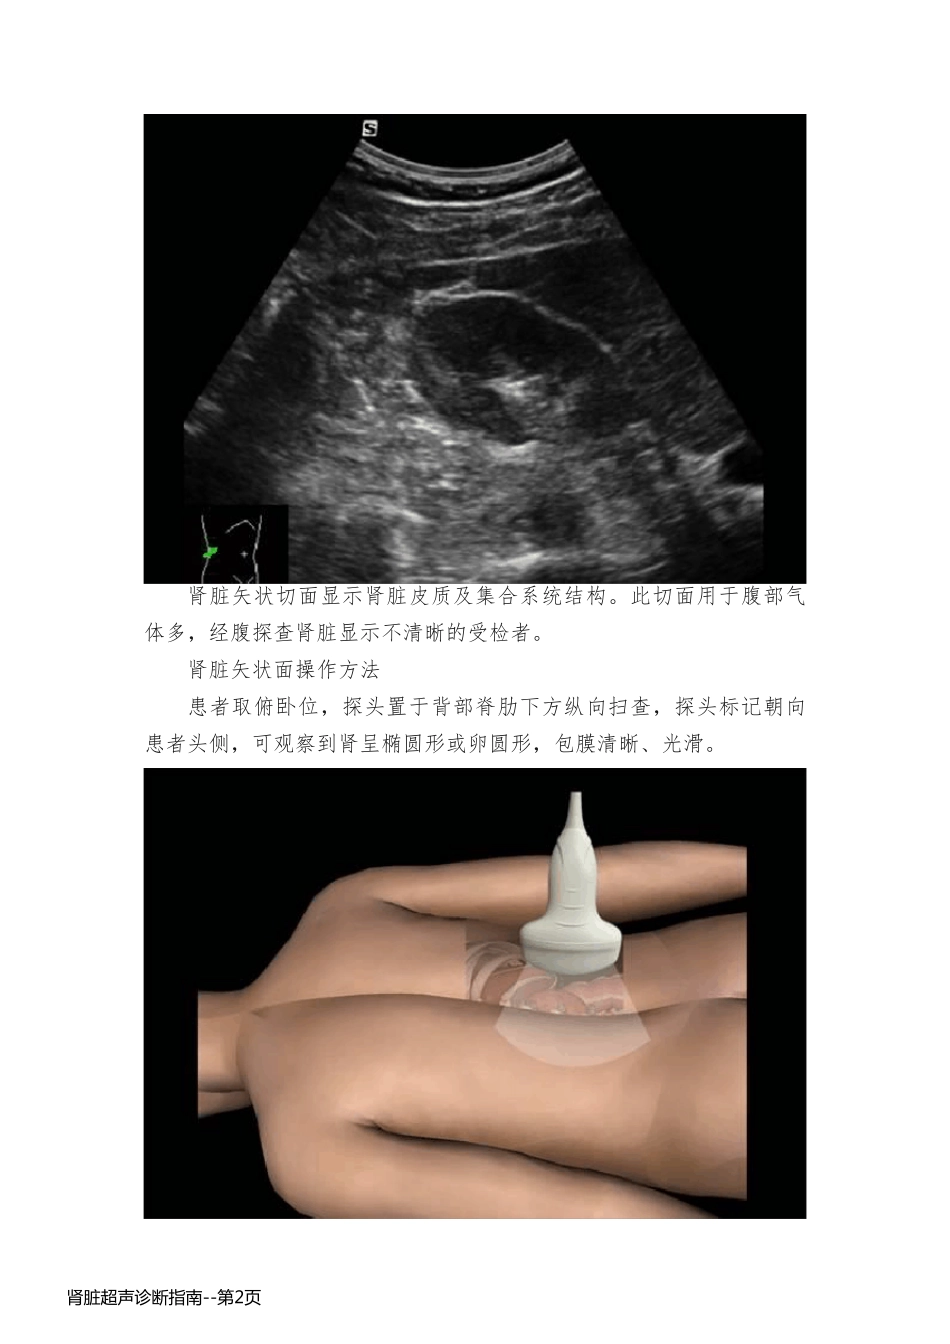

肾脏超声诊断指南 肾横切面、矢状切面 概述 肾脏横切面显示肾脏的横断面、肾门结构。右肾横切面其后方为腰大肌横断面,前方为肝右叶的横断面。 肾脏横切面测量肾脏前后径和厚径。正常肾宽5-6cm ,厚3-4cm 。 肾脏横切面对于位于肾包膜下或突出包膜外的病变如囊肿较长轴切面显示清晰。显示腰大肌病变。肾上极病变和肝右叶病变的鉴别。肾门病变的显示。 肾脏横切面操作方法 在上述肾冠状切面位置旋转探头90 度,上下移动探头并调整声束角度,可获得肾脏横断面图像。 肾脏的横断面在肾门部呈“马蹄铁”形。肾的周缘部位为均匀低回声,中心部分为不规则强回声。 肾 脏 超 声 诊 断 指 南 --第 1页肾 脏 超 声 诊 断 指 南 --第 1页 肾脏矢状切面显示肾脏皮质及集合系统结构。此切面用于腹部气体多,经腹探查肾脏显示不清晰的受检者。 肾脏矢状面操作方法 患者取俯卧位,探头置于背部脊肋下方纵向扫查,探头标记朝向患者头侧,可观察到肾呈椭圆形或卵圆形,包膜清晰、光滑。 肾 脏 超 声 诊 断 指 南 --第 2页肾 脏 超 声 诊 断 指 南 --第 2页 脾脏左肋间斜切 概述 脾脏呈三角椎体,位于腹腔的左上腹部,在膈肌之下,胃的左后方,左肾的前上方,横结肠之下,被第九、十、十一肋骨掩盖。 整个脾脏除脾门外,几乎都有腹膜掩盖。脾门是在脾脏内侧凹面的中部,为脾动脉、脾静脉及淋巴管出入脾脏之处,包有腹膜的脾动脉、脾静脉即构成脾蒂。超声现象能清楚的显示出脾门和脾门处血管(主要为脾静脉)的声像图。 左肋间斜切主要用于观察脾脏长轴切面,观察脾脏的大小、形态及内部回声。 探头 脾脏的超声检查一般选用凸阵(2-5MHZ )探头。 脾脏的超声的操作方法 患者右侧卧位或仰卧位,探头置于左腋前线至腋中线间的第9-11 肋间,探头与肋间隙平行,探头标记朝向患者左上方。调整探头角度,观察脾脏形态、内部结构、脾脏血管。 肾 脏 超 声 诊 断 指 南 --第 3页肾 脏 超 声 诊 断 指 南 --第 3页 肾 脏 超 声 诊 断 指 南 --第 4页肾 脏 超 声 诊 断 指 南 --第 4页 注:选择最大长径及有脾门部血管的切面为测量的标准切面。测量脾脏厚径和长径。厚径需测到最大径,即从脾门到膈顶部包膜。长径需测脾的实际长度,即从脾门处到上下极的脏面长度之和。正常脾脏的长度应小于 12cm ,厚度 2-4cm 。脉冲多普勒显示脾静脉为连续肾 脏 超 声 诊 断 指 南 --第 5页肾 脏 超 声 诊 断 指 南 --第 5页性流速曲线,可受呼吸等因素影响,血流流速范围为16 -25cm/s 。 肾 脏 超 声 诊 断 指 南 --第 6页肾 脏 超 声 诊 断 指 南 --第 6页